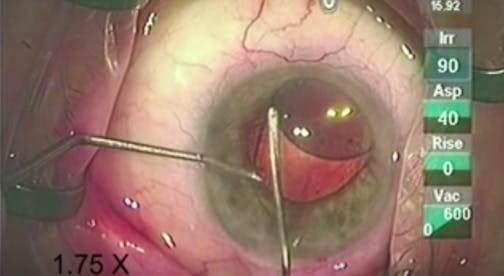

Morgagnian Cataract

Lisa Brothers Arbisser, MD